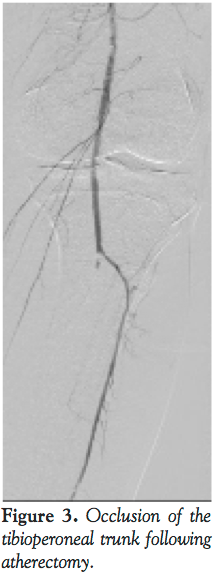

atherectomy system using 8 total runs (3 with blades down and 5 with blades extended). Audible decelerations were noted during the first 3 extended blade runs suggesting highly fibrotic or calcified plaque. Post atherectomy demonstrated significant debulking of plaque (Figure 2B). However, repeat angiography of the below the knee circulation now revealed acute occlusion of the left tibioperoneal trunk (Figure 3). To augment antiplatelet activity, intravenous eptifibatide was started. The 3-gram MiracleBros wire was redirected into the peroneal artery. A second 3-gram MiracleBros wire was directed through the occluded posterior tibial artery. Sequential aspiration thrombectomy was performed using a ProntoLP catheter (Vascular Solutions, Inc.) (Figure 4A), first through the tibioperoneal trunk into the peroneal artery and then similarly into the posterior tibial artery. The aspirate did not reveal any visible thrombus or macroscopic atherosclerotic debris but there was some improvement in flow through the posterior tibial artery (Figure 4B). Focal balloon angioplasty of the tibioperoneal trunk was performed using the 3 mm x 15 mm Maverick balloon (Boston Scientific) for 2 minutes (Figure 4C) resulting in restoration of flow in the infrapopliteal circulation (Figures 4D and 4E). The remaining mid SFA disease was treated with percutaneous transluminal angioplasty (PTA) and stenting. The patient was maintained on a heparin drip overnight. The following day, the patient demonstrated no signs of acute foot ischemia and both the posterior tibial and dorsalis pedis pulses were palpable.